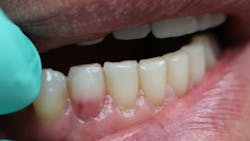

Have you ever laid the patient back, started your examination, and then noticed a tooth that just didn’t look right? You might even question what your eyes are seeing. Does that tooth look pink?

These pink spots are destructive and often insidious types of lesions that can occur either internally or externally on the tooth, resulting in significant loss of tooth structure. Both lesions have to do with a resorptive process that is occurring—often trauma-induced. When you discover these lesions, you can break down the resorptive processes based on their location: external or internal.

ECR can be differentiated from root caries due to its pink hue and tactile sensation. During the examination, you will find that the dentin surrounding an ECR lesion is usually hard, whereas decay/caries typically feels sticky. When a clinician performs probing around this type of lesion, it will typically bleed—often profusely—because of the highly vascular granulation tissue, a result of the resorptive process.